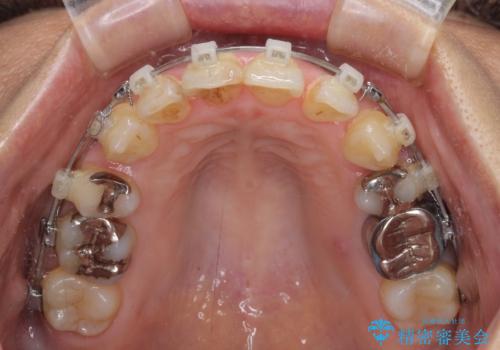

- クリアブラケット

- 2年2ヶ月

- 10-30回